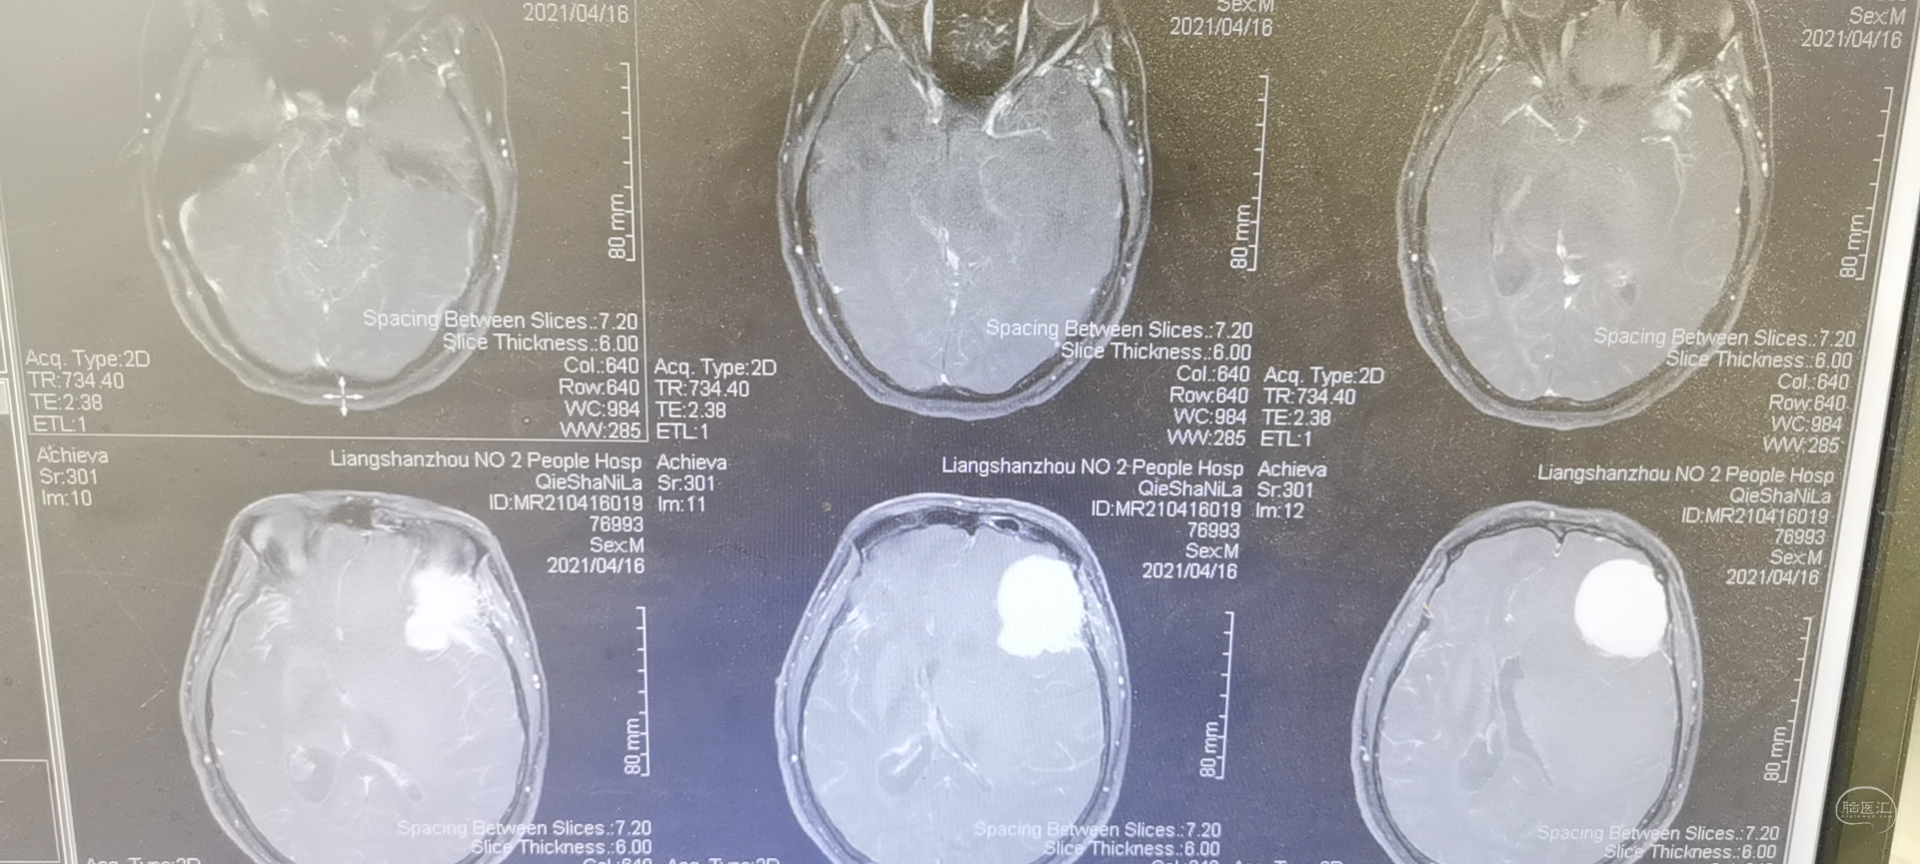

术前头颅MRI检查提示为左侧额叶占位性病变,增强强化均匀,似有脑膜征。考虑为脑膜瘤,蝶骨棘外侧型。

术后头颅MRI检查切除满意